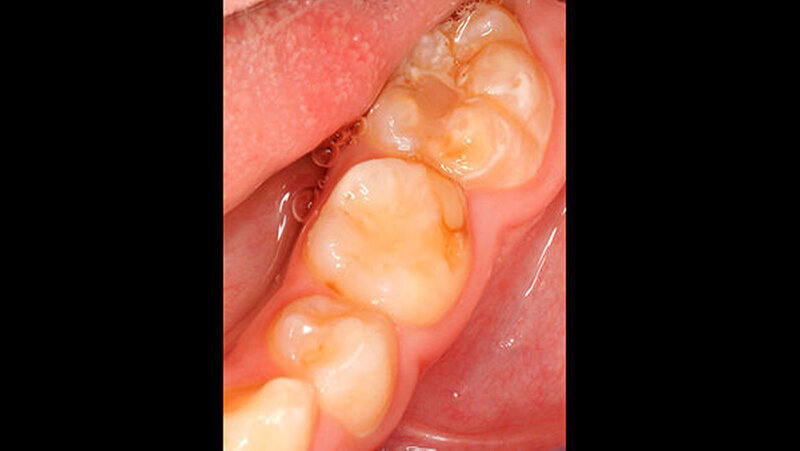

Der vor wenigen Jahren extrahierte Molar war der 16, anschließend war es im Laufe der Zeit im ersten Quadranten zu einer verhältnismäßig gleichmäßigen Lückenbildung gekommen. Der Zahn 17 war weitestgehend aufgewandert (Abbildung 2). Zahn 26 (Abbildung 3) wies eine umfangreiche adhäsive Restauration okklusal-bukkal auf. Zusätzlich dazu gab es aber auch weitere Areale mit veränderter Opazität von milchig-weiß (insbesondere palatinal) bis gelb-braun.